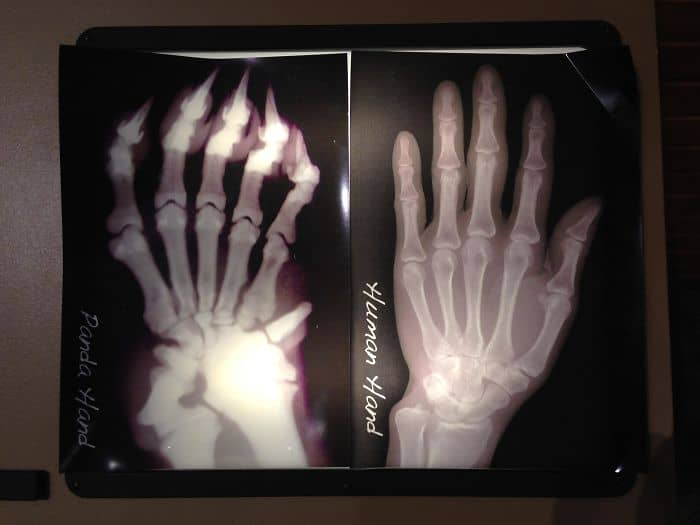

#74 X-Ray Of A Panda Hand vs. A Human Hand; Pandas Have An Extra “Thumb” To Help Grip Bamboo Stalks